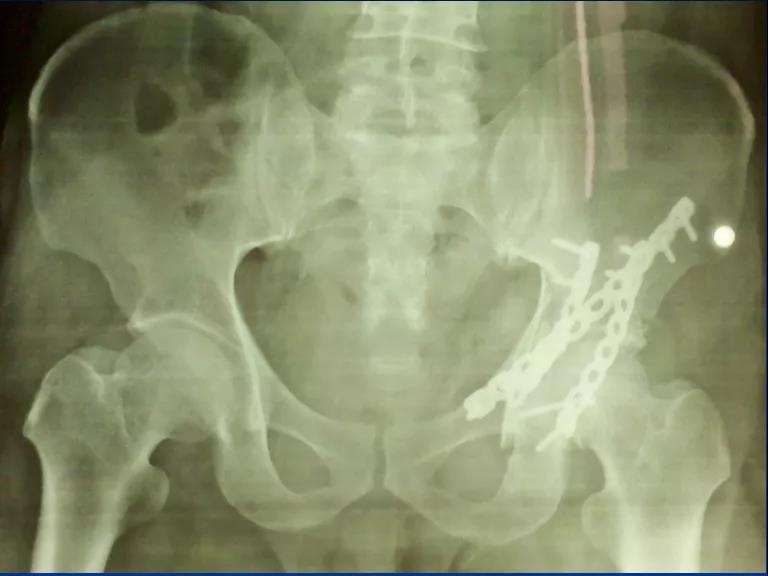

——典型案例——

微创插板病历后路有限切开,结合前路微创插板内